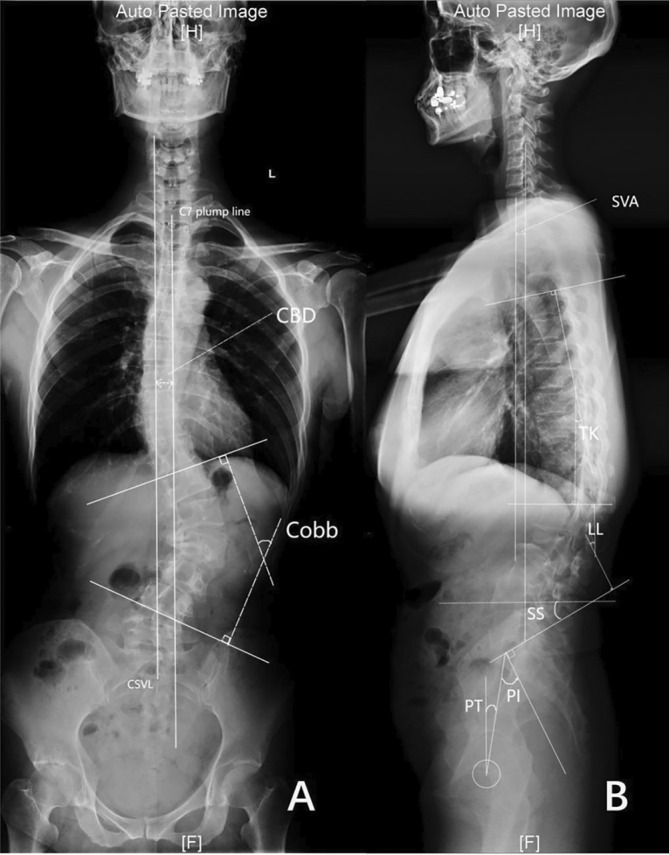

This retrospective study included 88 DLS patients underwent surgery from January 2019 to September 2021. The patients were divided into the OLIF group (n = 32) and the posterior group (n = 56). Comprehensive evaluations of clinical and radiological outcomes, including Cobb angle, coronal balance distance (CBD), sagittal vertical axis (SVA), thoracic kyphosis (TK), lumbar lordosis (LL), pelvic incidence (PI), pelvic tilt (PT), and sacral slope (SS) were conducted, with a subsequent subgrouping of OLIF group based on preoperative sagittal vertical axis (SVA) into Subgroup A (SVA ≤ 50 mm) and Subgroup B (SVA > 50 mm) for further analysis. The t‐test or Wilcoxon’s rank sum test is used to compare continuous variables, and the chi‐square test is used to compare categorical variables.

Clinical and Radiologic Evaluation

Data collected included age, gender, body mass index (BMI), T‐score of bone mineral density (BMD), follow‐up time, Lenke‐Silva classification, surgical details, and clinical and radiological results. Surgical details involved techniques used, fixation levels, fusion levels, operation time, estimated blood loss (EBL), drainage volume, length of hospital stay, and complications. Back and leg pain was measured with the visual analogue scale (VAS), Oswestry Disability Index (ODI), and Japanese Orthopedic Association (JOA) score both preoperatively and at the final follow‐up. Cobb angle, CBD, SVA, TK, LL, PI, PT, and SS were measured [ref. 12]. All digital radiographs were evaluated by two authors independently. The inconsistent results were measured again by a third, more senior surgeon. These doctors were only responsible for the measurements and were not aware of the study.